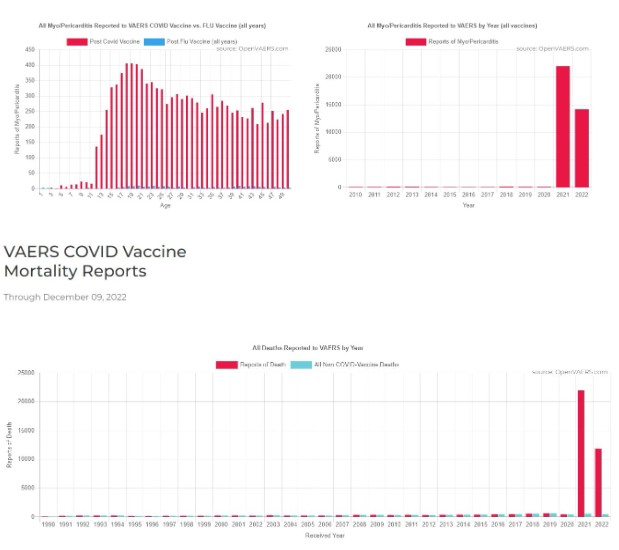

Los efectos conocidos de la miocarditis y otras lesiones cardíacas no solo han sido bien documentados en el público, sino que ahora están siendo reconocidos por el fabricante de la vacuna y la propia FDA. Y ahora que Twitter permite la “libertad de expresión” (más o menos), el mensaje está empezando a difundirse por todo el mainstream.

Recuerde esa anomalía en el número de lesiones notificadas, así como la disuasión, cuando considere el aumento de casos de miocarditis, así como de muertes:

Esto pasará a la historia como uno de los mayores crímenes de la historia del mundo.